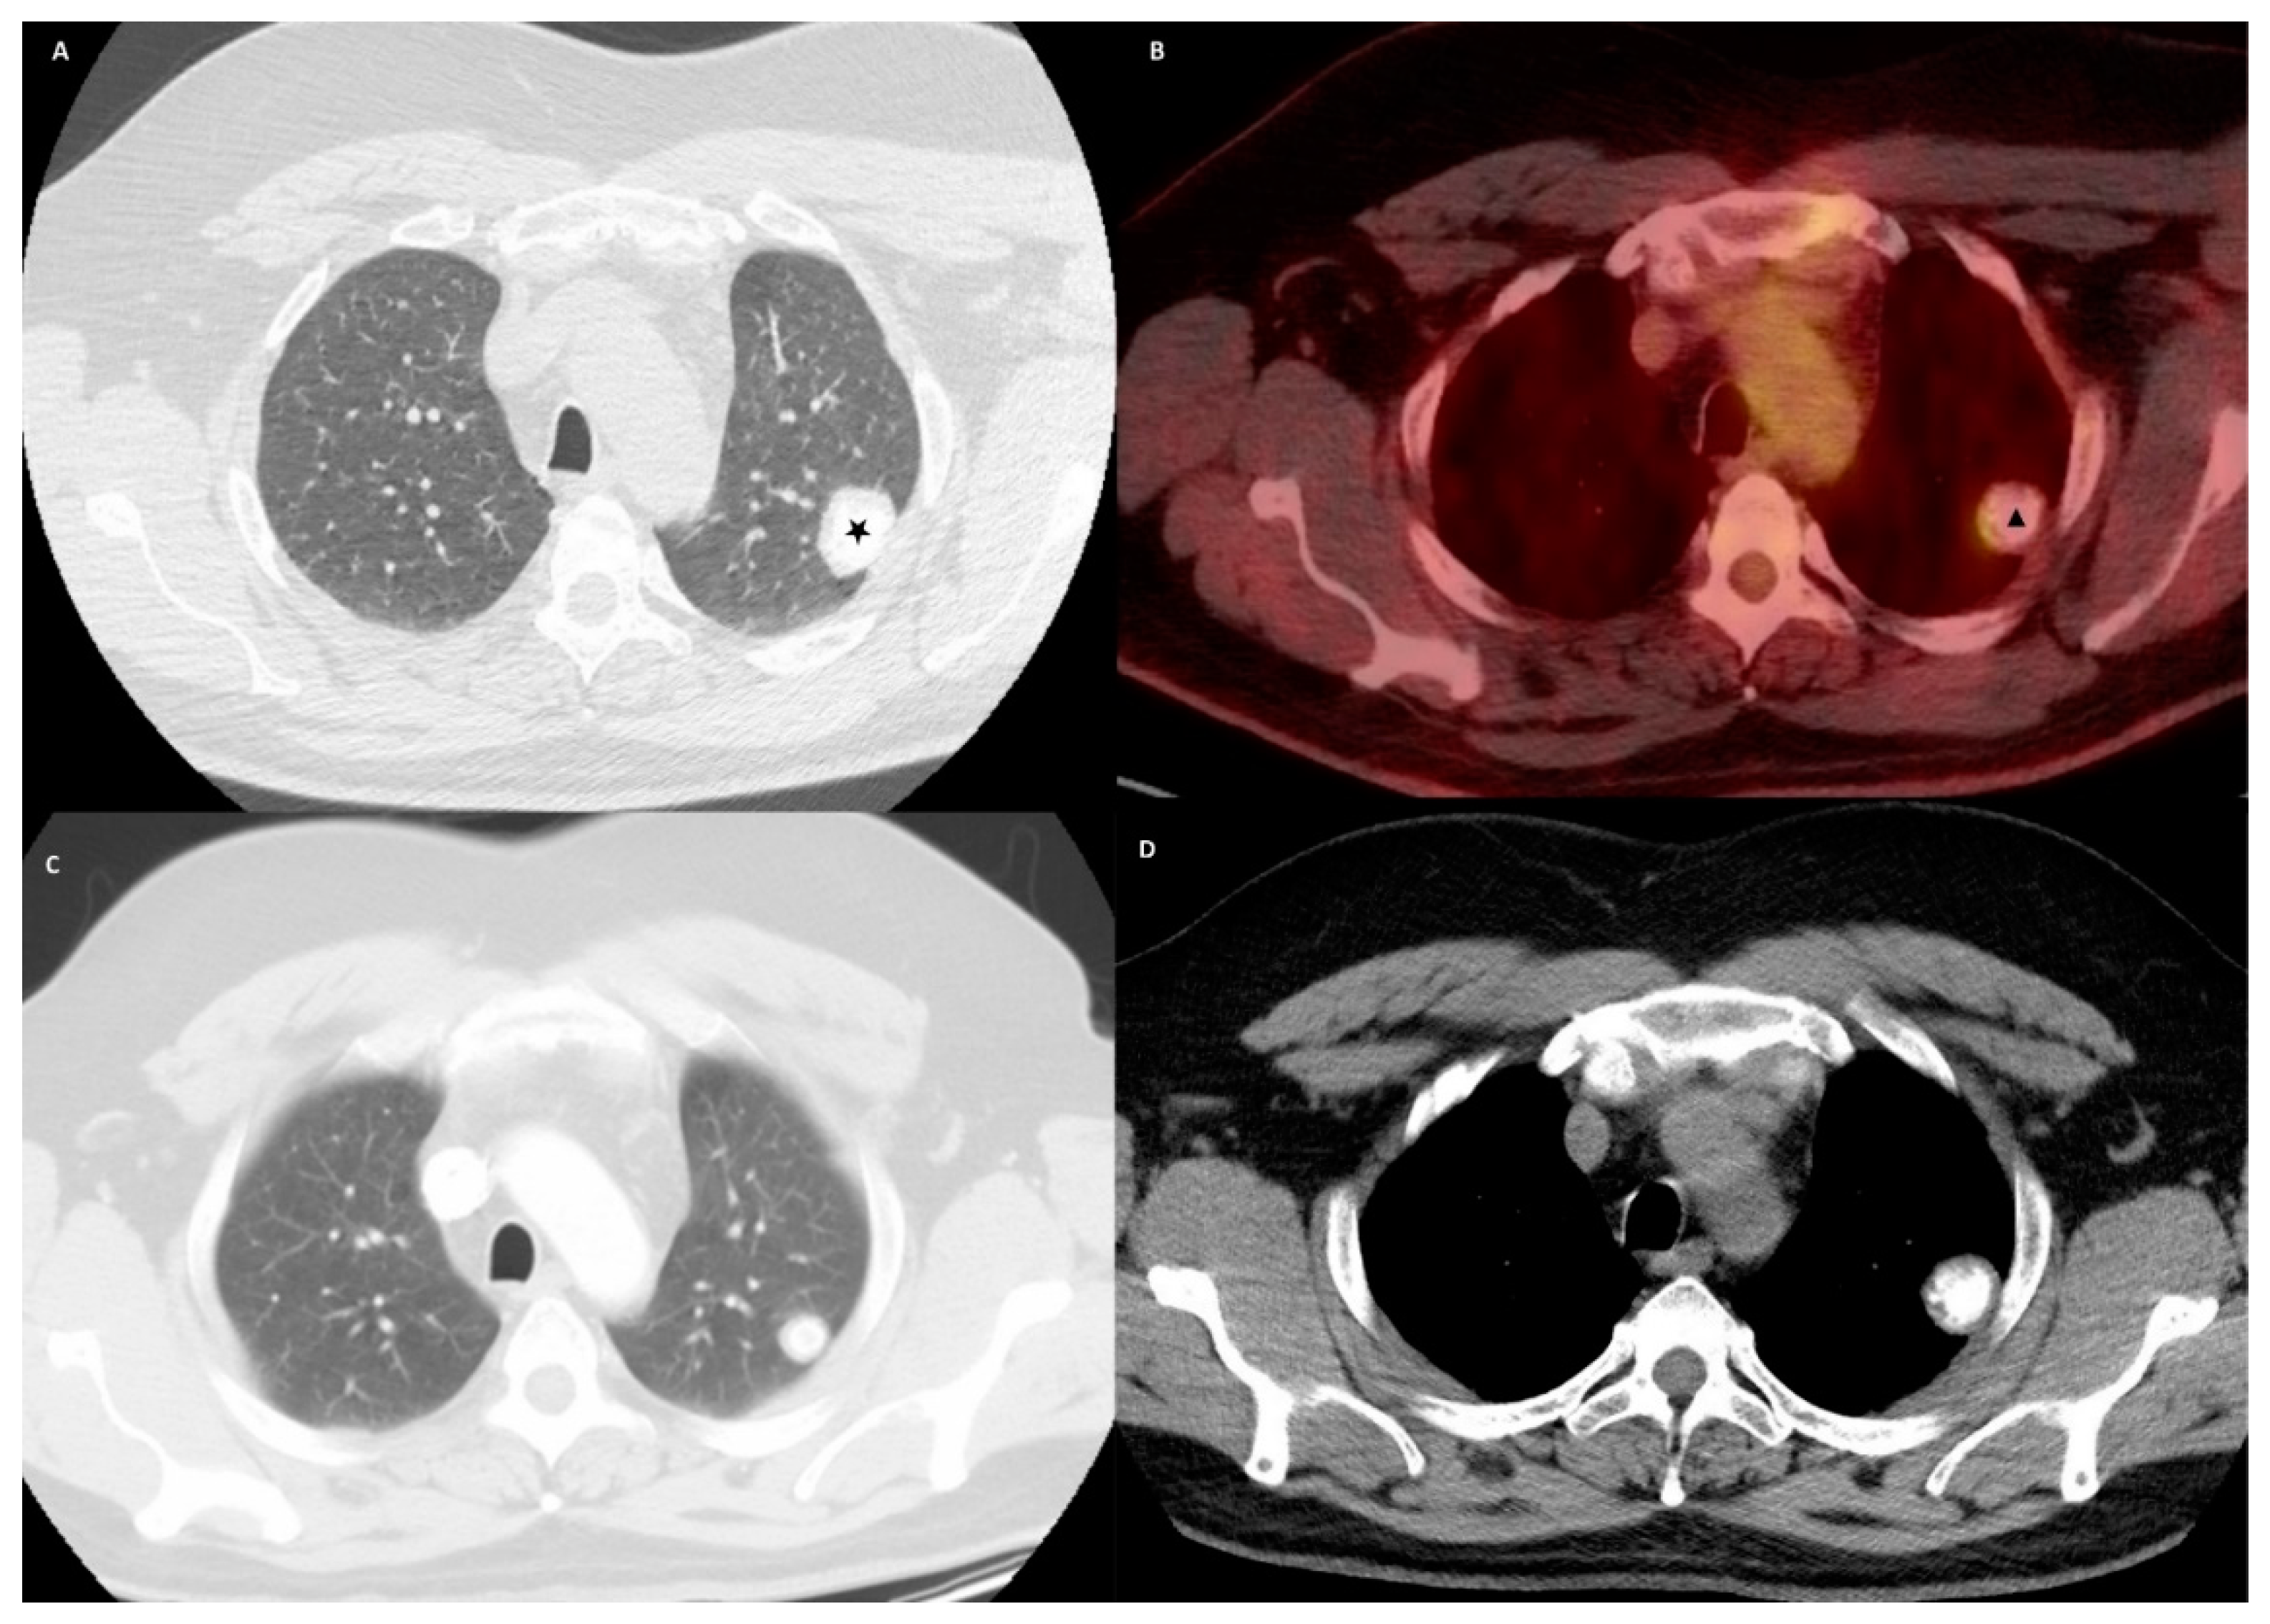

2. Case Presentation